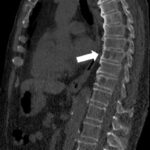

This study shows that sMRI is a valuable addition to conventional MRI for patients with vertebral fractures. Key points: • sMRI allows a reliable evaluation of vertebral body fractures. • sMRI has higher accuracy than standard-MRI for evaluation of...